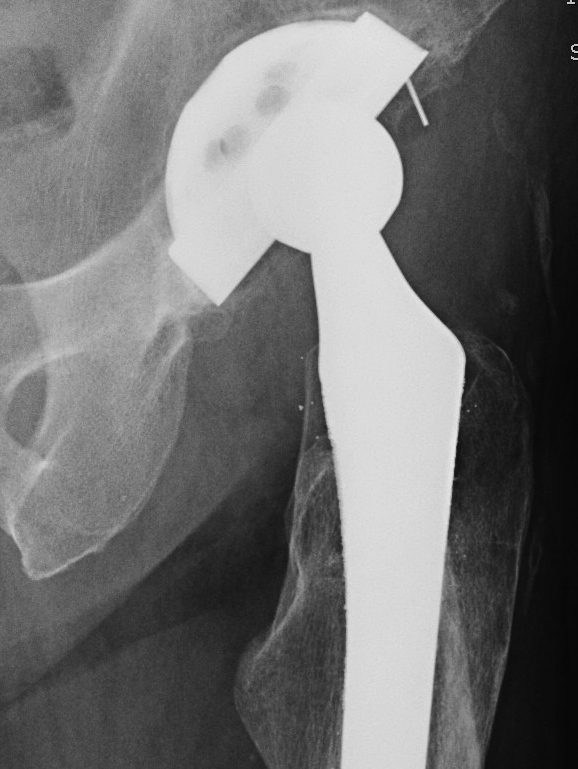

Liner exchange / augmentation

Technique

1. Exchange liner for elevated liner

2. Posterior liner augmentation device - screw onto old liner